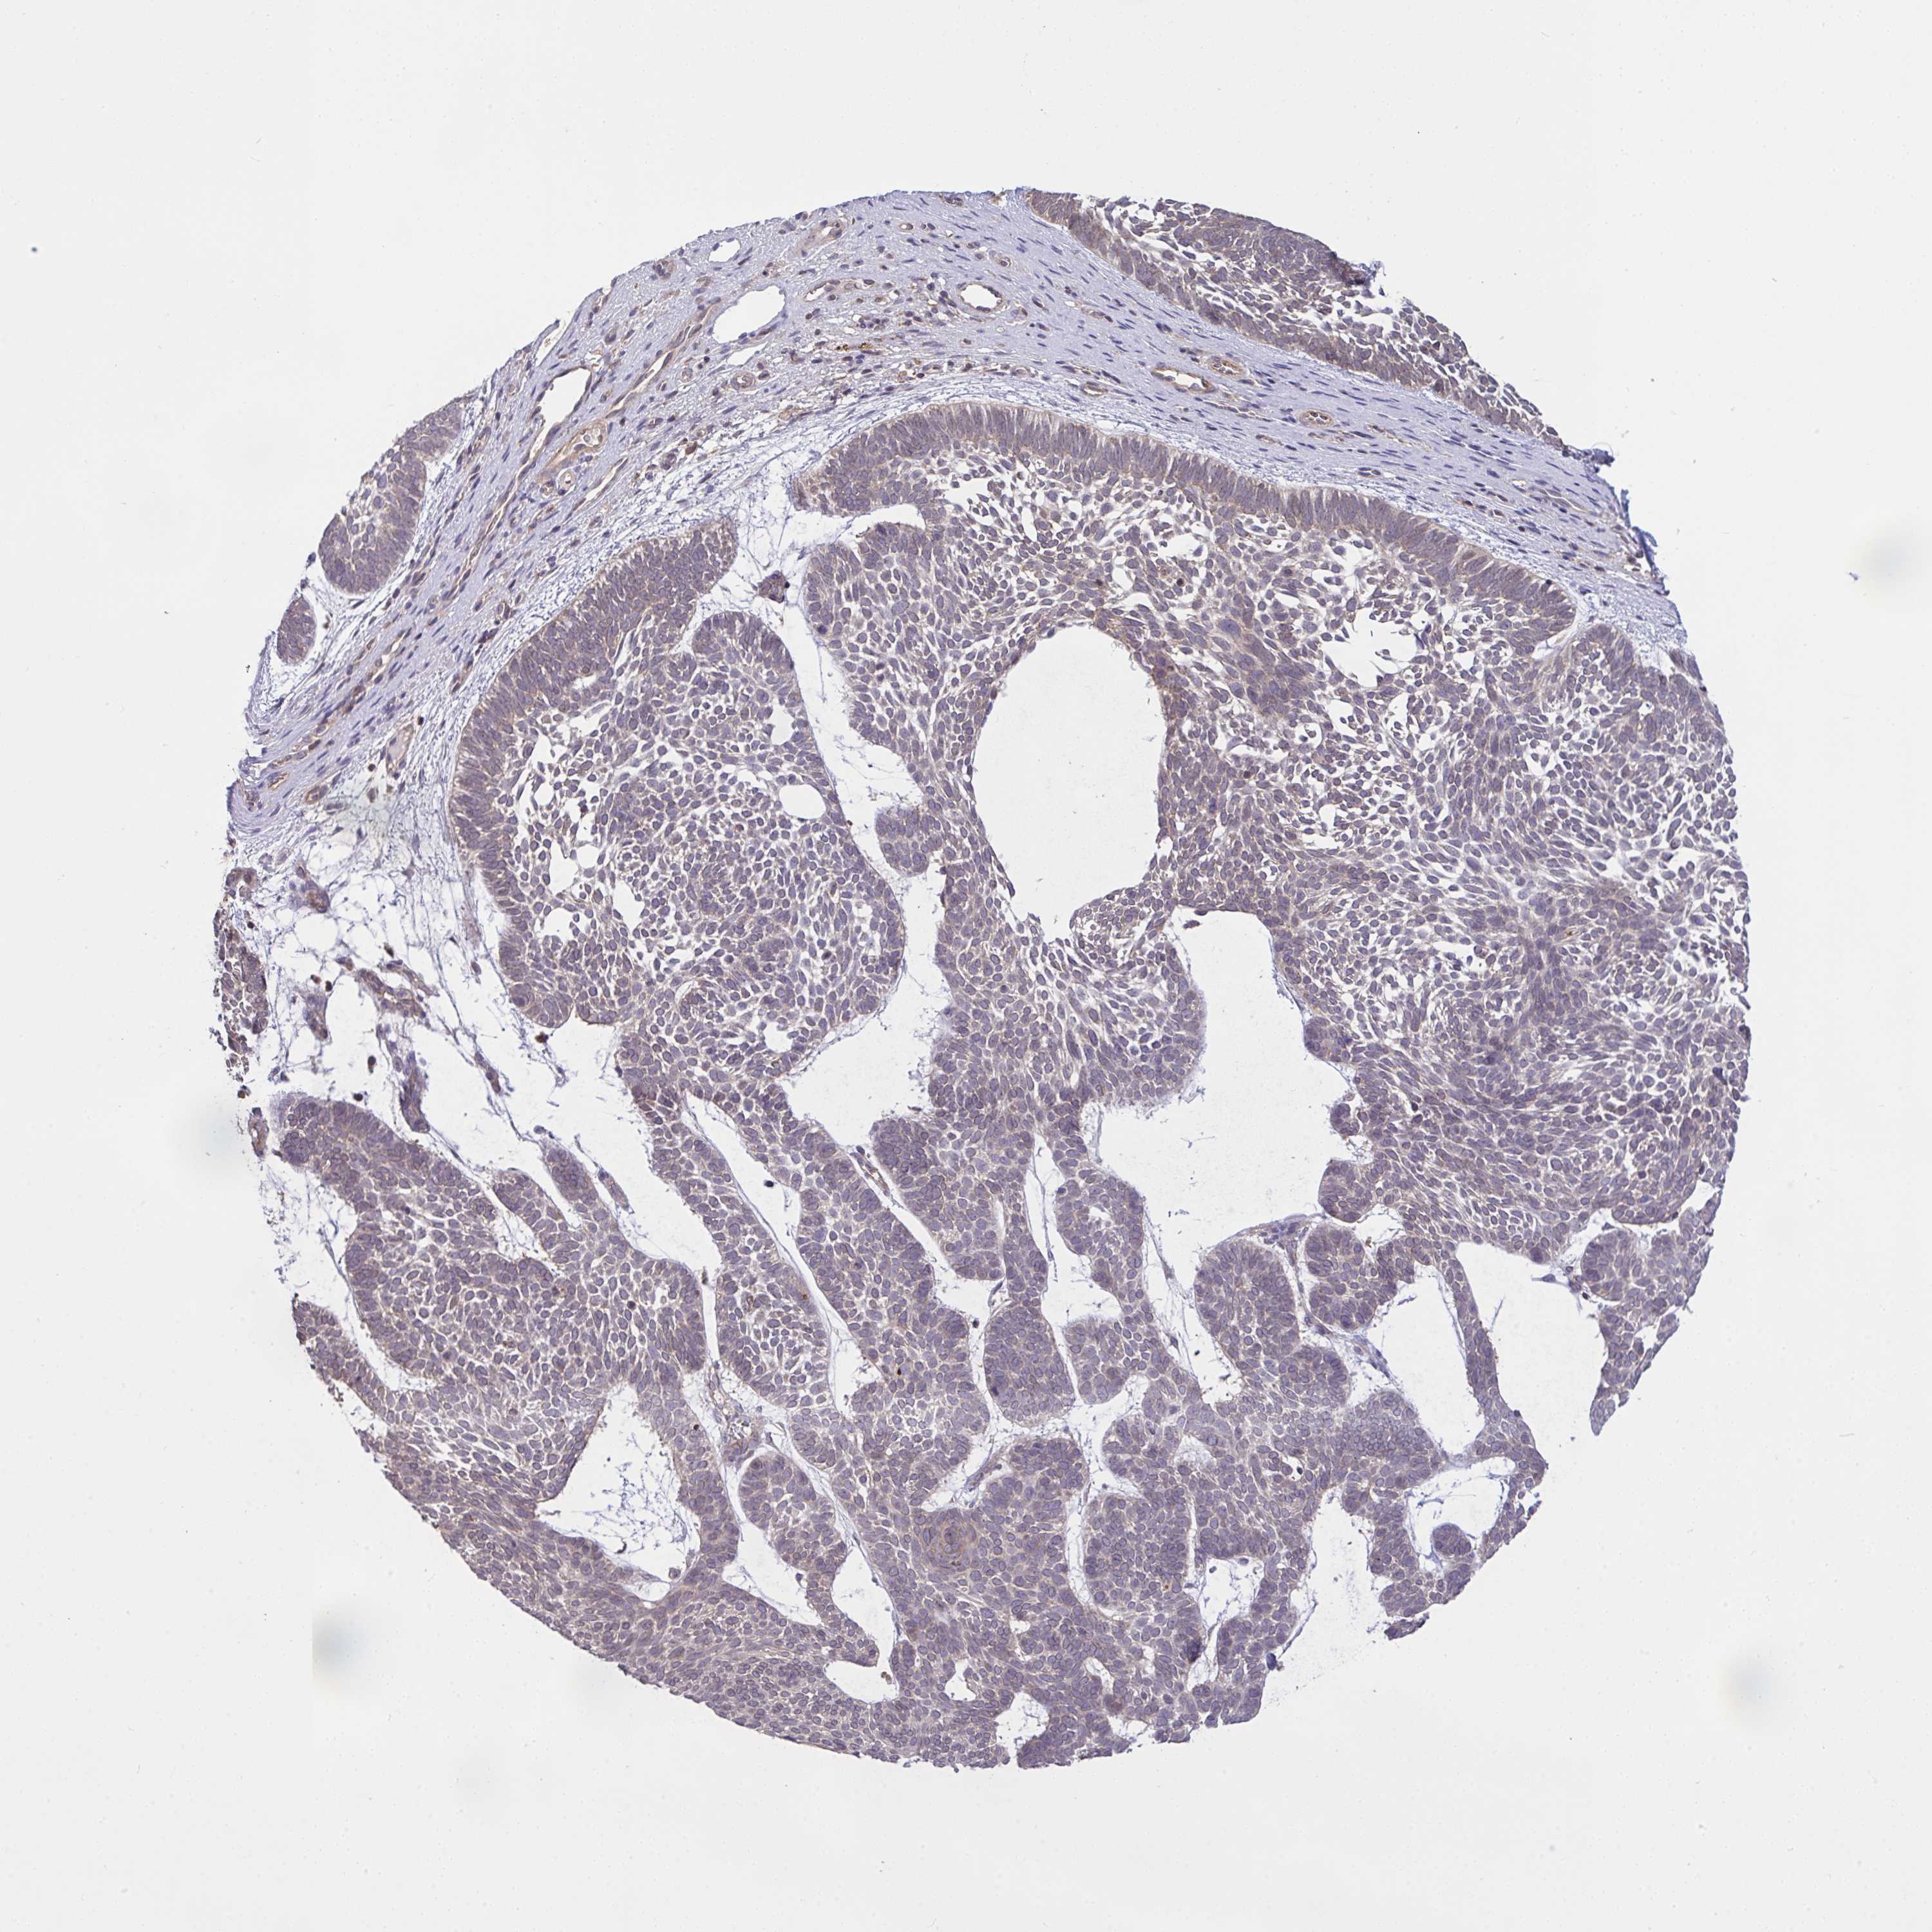

SKIN CANCER - Protein expressioni

A mouse-over function shows sample information and annotation data. Click on an image to view it in a full screen mode. Samples can be filtered based on level of antibody staining by selecting one or several of the following categories: high, medium, low and not detected. The assay and annotation is described here.

Antibody stainingi

Antibody staining in the annotated cell types in the current human tissue is reported as not detected, low, medium, or high, based on conventional immunohistochemistry profiling in selected tissues. This score is based on the combination of the staining intensity and fraction of stained cells.

Each image is clickable and will lead to virtual microscopy that enables deeper exploration of all samples and also displays staining intensity scores, fraction scores and subcellular localization as well as patient and tissue information for each sample.

Antibody HPA044244

Antibody HPA058777

Antibody CAB020694

Squamous cell carcinoma, NOS